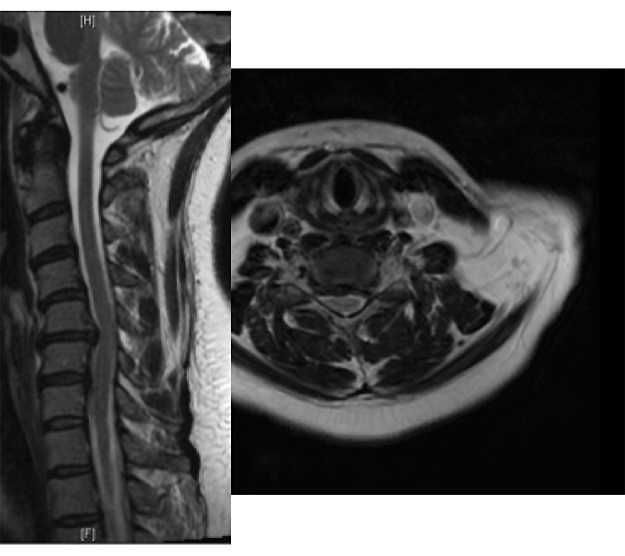

The intervertebral disc is a shock absorber that is located between the bony vertebral bodies in the neck, upper and lower back. It is composed of a firm outer layer and a gelatinous inner layer. When the outer layer is injured, the inner layer is extruded and can result in a pinched nerve. While common in professional football players, these injuries are not limited to contact sports as Major League Baseball players such as Nick Markakis and Prince Fielder have all been diagnosed with a herniated disc in their neck.

Rarely, herniated discs in the neck can lead to compression on the spinal cord. This often leads to difficulty with balance, numbness and tingling in the hands, weakness is the arms and legs and rarely difficulty controlling one’s bowels and bladder. If any of these symptoms are present, athletes should seek immediate medical care, as prompt surgical intervention may be needed.